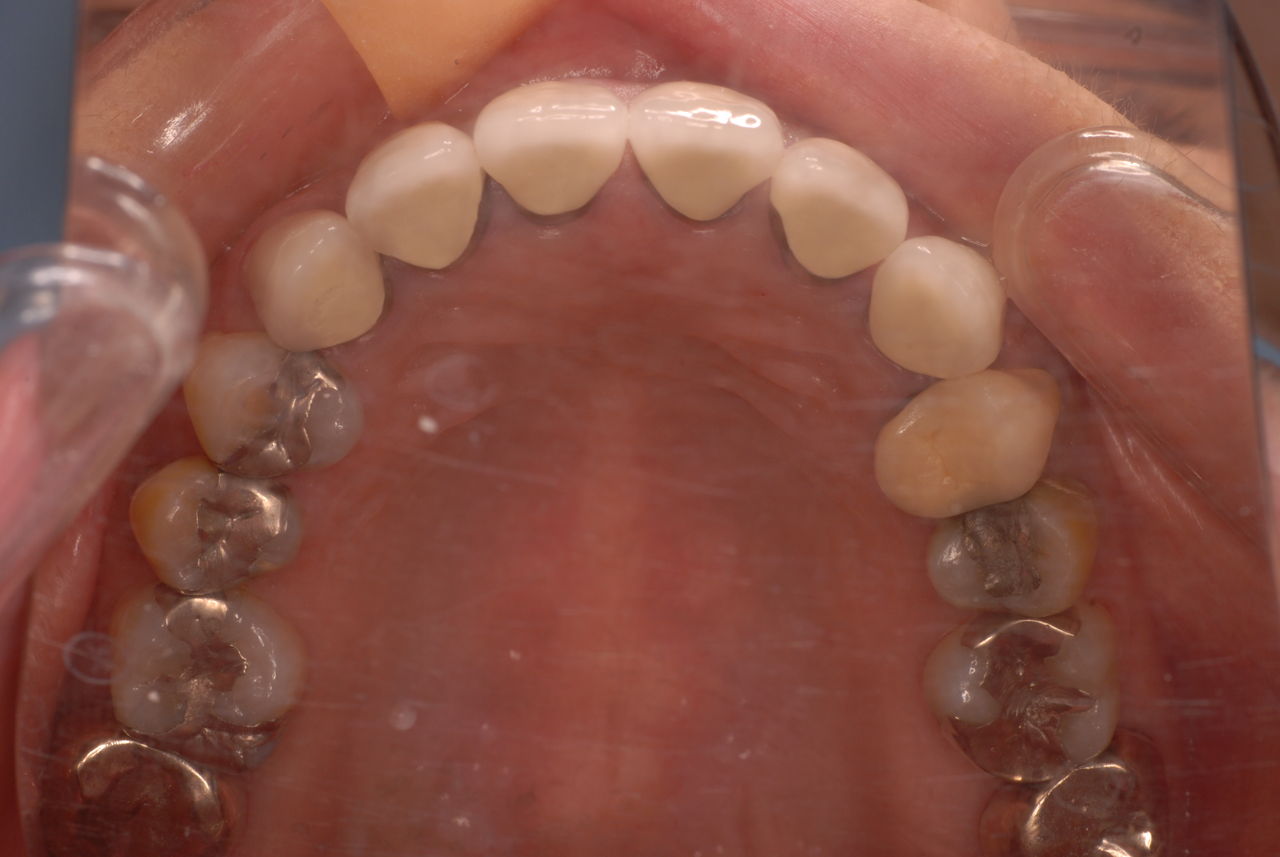

食べカスまみれで歯周病に罹患しています。

下の歯は数本存在しますが、全て虫歯と歯周病に犯されていました。